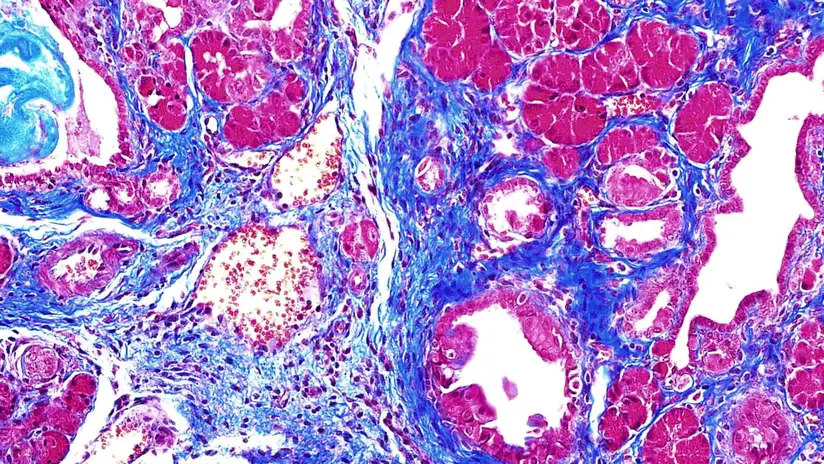

正常健康的胰腺细胞保持恒定的SRSF1水平(染成红色),但在PDAC中,这些水平的增长失去了控制。资料来源:Krainer实验室/冷泉港实验室